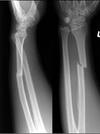

Grey Turner’s sign

Flank ecchymosis

Acute pancreatitis